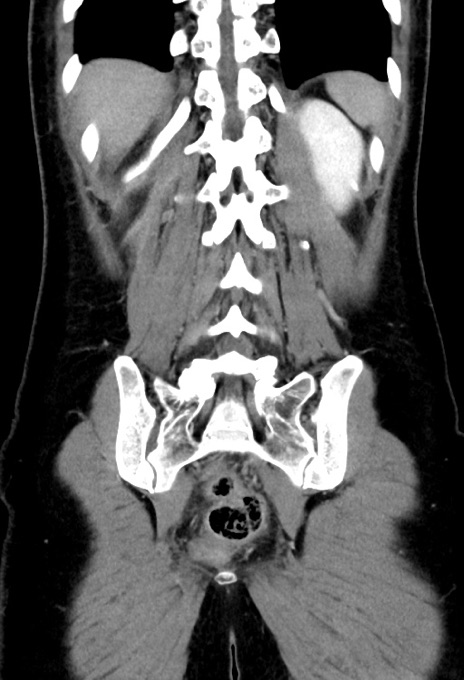

症例17(冠状断像)

【症例】20歳代女性

【主訴】嘔吐、下腹部痛

【現病歴】昨日夕食後に嘔吐し下腹部痛が出現。本日になっても嘔吐持続し改善しないため来院。

【身体所見】意識清明、BT 37.2℃、BP 108/67mmHg、腹部:平坦、やや硬、下腹部正中から右にかけて圧痛あり、反跳痛軽度あり、tapping pain(+)。

【データ】WBC 13600、CRP 14.94